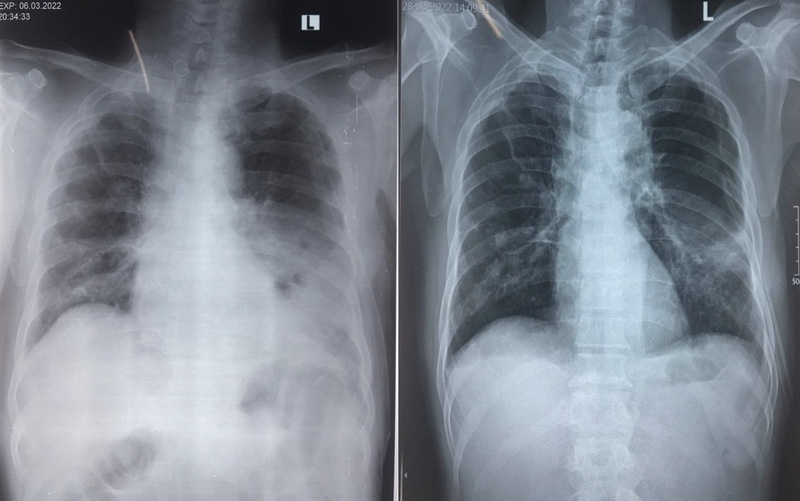

Sau khi thăm khám, chụp X-quang ngực kết hợp chụp cắt lớp vi tính và làm các xét nghiệm chuyên sâu, BSCKI. Nguyễn Hồng Hải – Trưởng Khoa Nội 2 nhận định bệnh nhân bị áp xe phổi.

Sau 2 ngày điều trị nội khoa, bệnh nhân xuất hiện thêm tình trạng tràn khí màng phổi. Các y bác sĩ đã nhanh chóng mở màng phổi dẫn lưu khí cho người bệnh.

Sau gần 1 tháng điều trị tích cực, bệnh nhân đã tiến triển tốt dần lên từng ngày, các triệu chứng của bệnh đã hết, người bệnh ăn ngủ, đi lại tốt, các chỉ số cận lâm sàng đã cải thiện rất tốt và trở lại chỉ số bình thường.